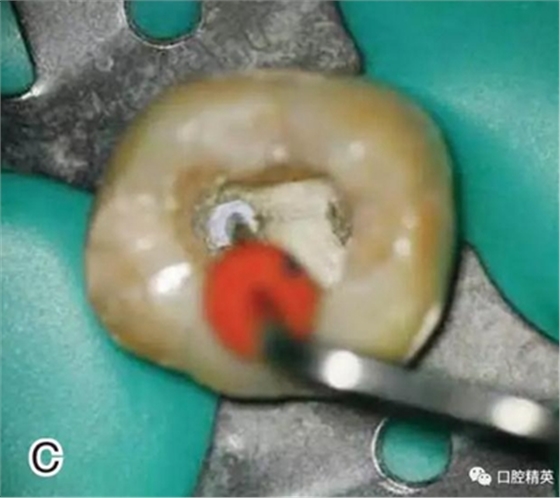

5、去除根管口外牙膠尖

調(diào)節(jié)好攜熱器的工作溫度,將攜熱器工作尖放置在根管口,啟動(dòng)加熱源,去除根管口外多余的牙膠尖部分,用大號(hào)的垂直加壓器在根管口向根方輕輕加壓(圖5)。

圖5 去除根管口外牙膠尖,A、B.?dāng)y熱器尖去除根管口處的牙膠尖

C、D.大號(hào)垂直加壓器輕輕加壓